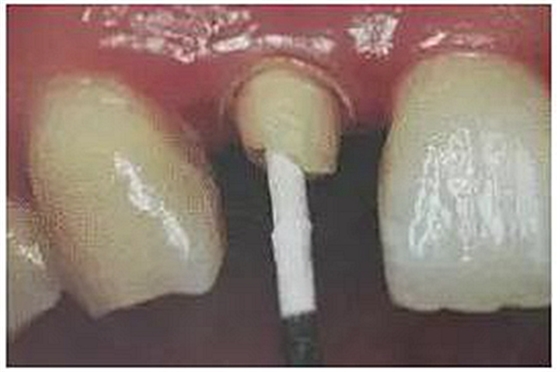

1. 沖洗預(yù)備根管

臨床多數(shù)醫(yī)生在樁道預(yù)備上習(xí)慣于干燥預(yù)備根管。

(干燥預(yù)備根管)

這樣容易破壞根管的牙本質(zhì)結(jié)構(gòu),也可形成較厚的玷污層,影響樹脂水門汀與牙體組織的粘接。

(沖洗預(yù)備根管)

應(yīng)選擇沖洗預(yù)備根管,防止牙膠及封閉劑粘連附著于根管壁形成第二層玷污層(根管治療時(shí)形成的玷污層稱為第一玷污層),利于樹脂水門汀與根管牙本質(zhì)的粘接。